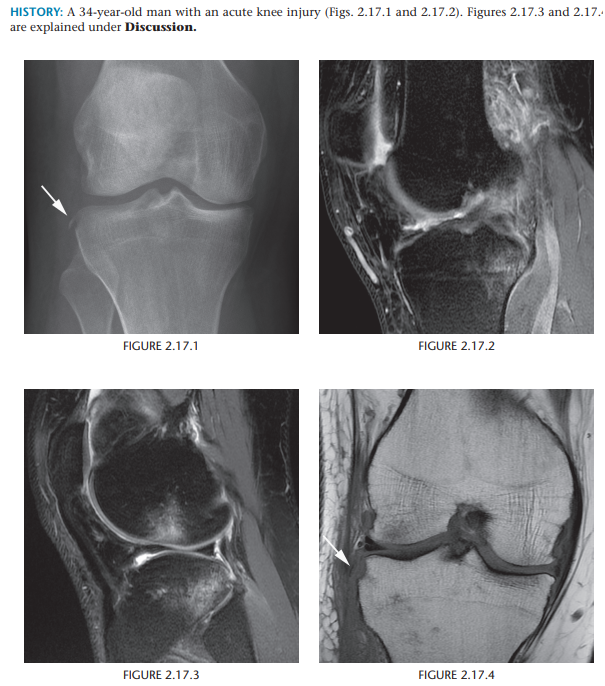

Segond fracture

Avulsion Fracture - lateral tibial plateu

90% ACL tear association